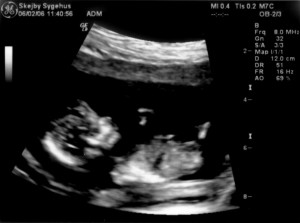

Ultralydsskanning den 6. februar 2006

Vi har i dag været på Skejby Sygehus og få foretaget en ultralydsskanning af baby. Der var kun én (pyh)! Baby blev målt og gennemset for eventuelle misdannelser. Der blev set efter at kraniet var begyndt at blive dannet og at der var to hjernehalvdele. Vi så to arme og to ben og der var fem fingre på den hånd vi så. Vi så også hjertet slå. Til sidst blev der blev målt bredden på nakkenfolden for at vurdere risikoen for mongolisme. Konklussionen var, at alt var som det skulle være. Du kan se de billeder vi fik fra skanningen herunder.